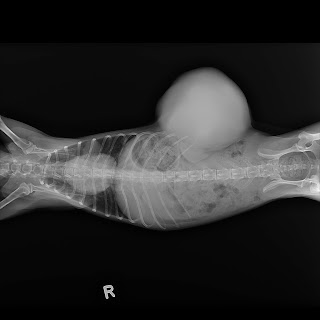

3184. A 30-month-old dwarf hamster is operated for a tumour

This Myanmar man has several dwarf hamsters.

He decided to get the dwarf hamster operated despite the high anaesthetic risk and the very old age. The dwarf hamster lives up to 2.5 to 3 years and this one was 26 months old. Some pet owners will save on financial costs as the life span is near the end.

But he is not a calculating man.

"I get the operation done to make his life less painful," he told me.

"Doc," my assistant informed me during pre-operation preparation. "This is an abscess!"

"There is a big pimple seen," I said. "You could be correct. But it could be an encapsulated abscess or an infected tumour."

Surgery and gas anaesthesia revealed an infected tumour. Never judge a book by its cover.